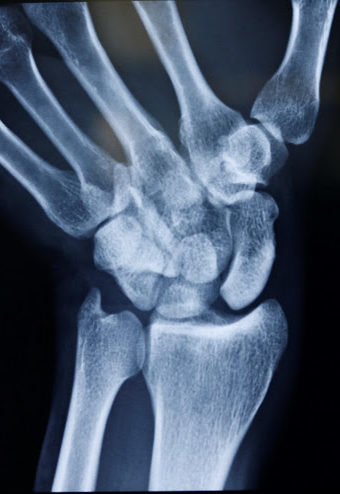

Skafolunat bağ yaralanmaları en sık görülen el bileği yaralanmalarıdır. Bu bağ skafoid ve lunat kemiği bir arada tutar. Bu bağın bozulması skafolunat instabilitesine neden olur. Geç aşamalarda skafoid ve lunat kemik arasında bir boşluk oluşur ve skafolunat ayrışması olarak bilinir.

Skafolunat ekleminin ayrıldığını gösteren bileğin stresli görünümü